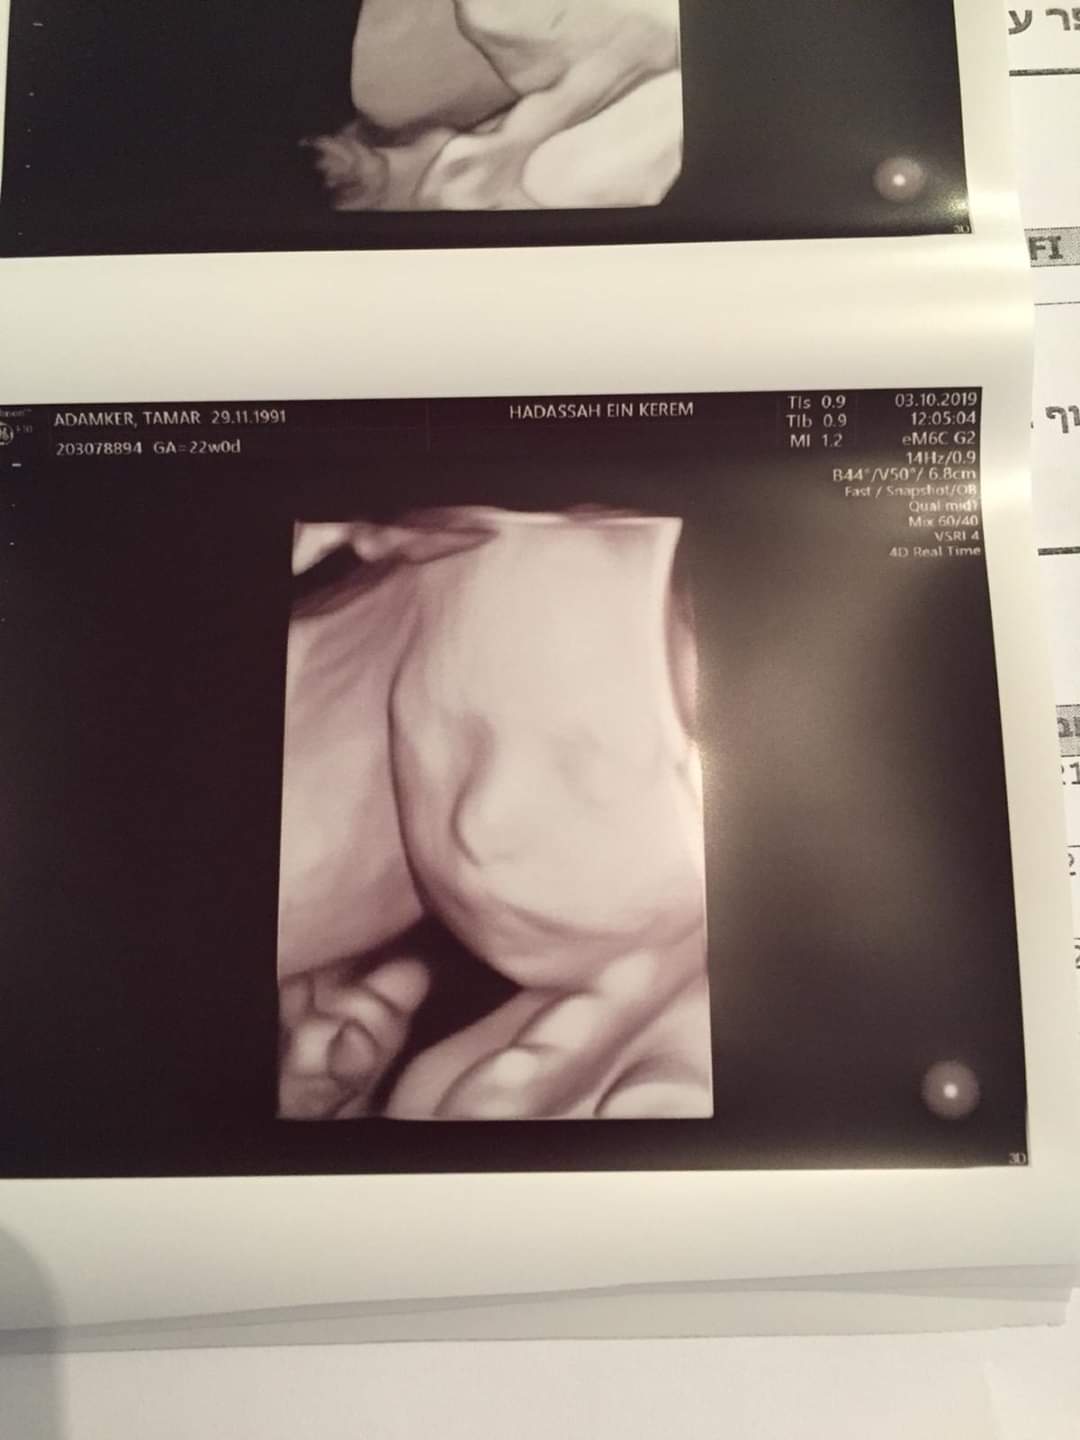

"זה ארוך", פותח האב השכול את תיאור השתלשלות העניינים הטעונה, "אבל אני מבקש שתקראו עד הסוף: לפני 9 חודשים, כשתמרי אשתי הייתה בחודש החמישי להריון עם הבת השלישית שלנו, הגענו לבית החולים הדסה עין כרם בירושלים. זו הייתה אמורה להיות בדיקה שגרתית, שבסופה הולכים הביתה כאילו לא קרה דבר. כך לפחות חשבנו".

"אבל ד"ר נג'ארי, רופא בכיר במחלקת אולטסאונד נשים - ראה אחרת" ישבנו מולו בחדר הקטן בקומה הראשונה בבניין בבית החולים, והתחלנו לשמוע הגדרות רפואיות שמעולם לא הכרנו קודם. טריזומה 18, תסמונת אדוארדס ועוד. רוב התינוקות שאובחנו בתסמונת קשה זו לא שרדו את ההיריון. 40% חיים רק שבוע ורק 10% חיים מקסימום שנה אחת, הוא סיפר לנו. קשה לתאר מה עברנו באותם רגעים. זיעה קרה בכל חלקי הגוף, סחרחורות וכל דבר שרק גרם לחוסר שיווי משקל. פיזית ונפשית".